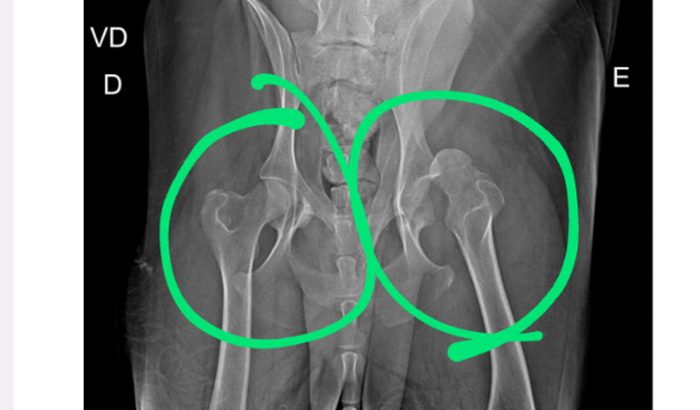

Meu nome é Rafael Gondim e estou aqui para pedir a ajuda de vocês em um momento muito difícil. Meu querido cachorro, Stark, recentemente foi diagnosticado com uma condição médica séria (displasia coxofemoral) que requer uma cirurgia urgente.